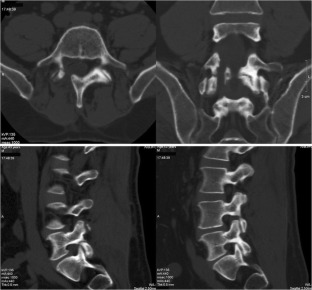

Atypical, unusual, and misleading imaging presentations of spondylolysis

Although lumbar spondylolysis is a widely known and easily recognizable condition in its typical presentation, there are some less well-known forms that may occasionally be challenging and/or demand special attention on imaging. Examples include: acute and/or incomplete lesions; unilateral defects; lesions at unusual levels (cervical, upper lumbar, and multi-level spondylolyses); iatrogenic lesions; non-isthmic spondylolysis; and spondylolysis related to underlying diseases. In addition to their atypical, uncommon or confusing imaging presentations, these forms of spondylolysis are far rarer than the classic type and have been described, to a great extent, in the surgical literature, thus reducing the awareness of radiologists about them and raising the potential for misdiagnosis and inadequate treatment. In this review the authors address these special manifestations of spondylolysis, stressing the more important features to be considered in the differential diagnosis and the impact of a precise diagnosis of spondylolysis on the patient’s care.